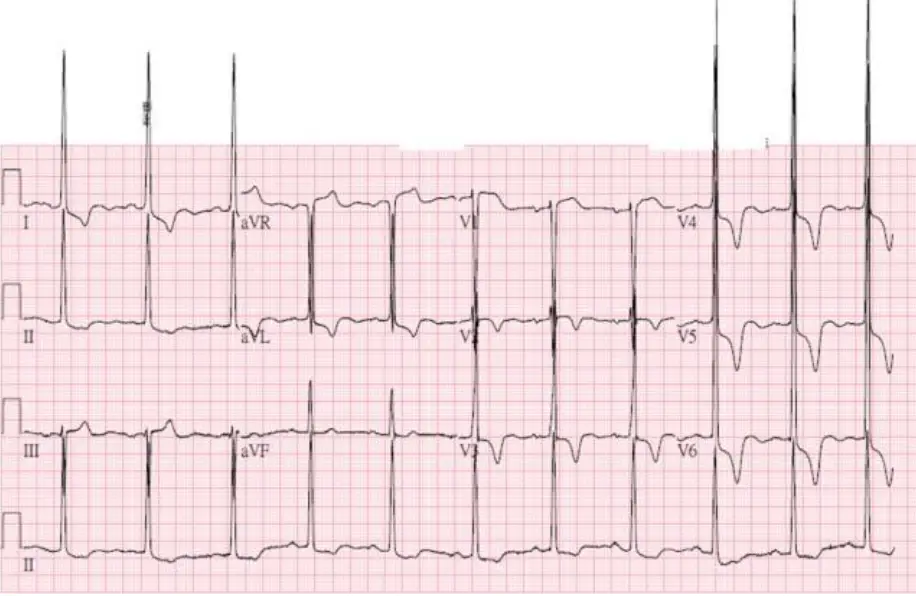

選項A 心電圖(心電圖A): 此12導程心電圖顯示各導程 QRS 波幅明顯偏低(limb leads 電壓低,即肢導程 I、II、III、aVL、aVF 的 QRS 波幅普遍 <5 mm),並可見胸前導程 V1–V3 呈現 QS 型態(pseudo-infarct pattern,偽梗塞型),整體呈現「低電壓(low voltage)合併偽梗塞型」的心電圖特徵。這是 AL 型心臟類澱粉沉積症最典型的心電圖表現——類澱粉蛋白浸潤心肌造成電傳導異常,使 QRS 電壓降低,同時增厚的心室壁在超音波上顯示心肌肥厚,形成「電壓-質量不匹配(voltage-mass discordance)」現象。選項A 與心臟類澱粉沉積症的懷疑吻合。